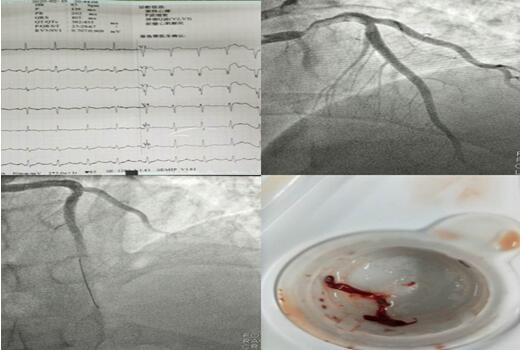

3個夜晚,3段急促的電話鈴聲打破了夜的寂靜,電話另一端傳來家屬的焦急與擔(dān)心。在接到胸痛中心電話的第一時間,3個夜晚的值班醫(yī)生立即進(jìn)行各項(xiàng)準(zhǔn)備,通知當(dāng)班護(hù)士備好讓搶救物品及藥品。患者被送達(dá)到科室同時啟動導(dǎo)管室,進(jìn)行術(shù)前相關(guān)檢查,明確手術(shù)指征、與患者家屬談話說明病情。 3個不同的夜晚,無影燈下卻站著同樣的2個人,崔旭輝主任與張洪亮醫(yī)生正在爭分奪秒的搶救患者的生命。他們?yōu)槠渲袃擅颊哌M(jìn)行了支架植入術(shù),為另一名患者抽吸出血栓。術(shù)后3名患者生命體征均平穩(wěn),癥狀較前緩解。

2月11日,患者毛某行CRT-D術(shù),該患者是一位69歲的男性,因勞力性胸悶、氣短入院,多次因心衰于當(dāng)?shù)蒯t(yī)院住院治療,因疫情影響,輾轉(zhuǎn)來到我院,入院后行冠脈造影提示正常,結(jié)合心臟超聲,診斷為擴(kuò)張型心肌病,給予強(qiáng)心、利尿、擴(kuò)冠后心衰糾正但不明顯。崔旭輝主任指出:該患者左室射血分?jǐn)?shù)降低(LVEF28%),NYHA心功能Ⅳ級,左束支傳導(dǎo)阻滯,QRS增寬大于120ms,有行CRT-D指征,即通過雙心室起搏器同步刺激左、右心室再同步化治療及埋置性心臟除顫器以改善心功能、治療惡性心律失常。術(shù)后患者QRS波群時限縮短、癥狀明顯改善?;颊叱鲈寒?dāng)天,科室收到來自患者家屬的感謝信,這份感謝信是對我們最好的禮物,是對我們工作的肯定和贊許。